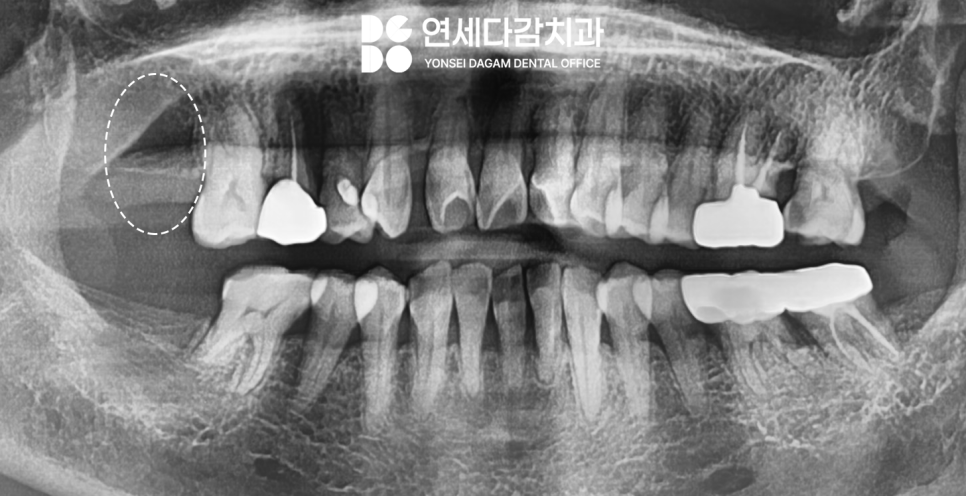

상악동저 피질골을 활용한

접근법이 잘 적용됐음을

확인할 수 있었습니다.

이후 고정체와 주변

골조직이 골 유착되는 과정을

충분히 기다렸습니다.

골다공증으로 인해

일반적인 경우보다

더 신중한 관찰이 필요하여

과정이 오래 걸렸지만

안정적으로 치유되어

최종 보철물도 무사히 완성할 수 있었습니다.